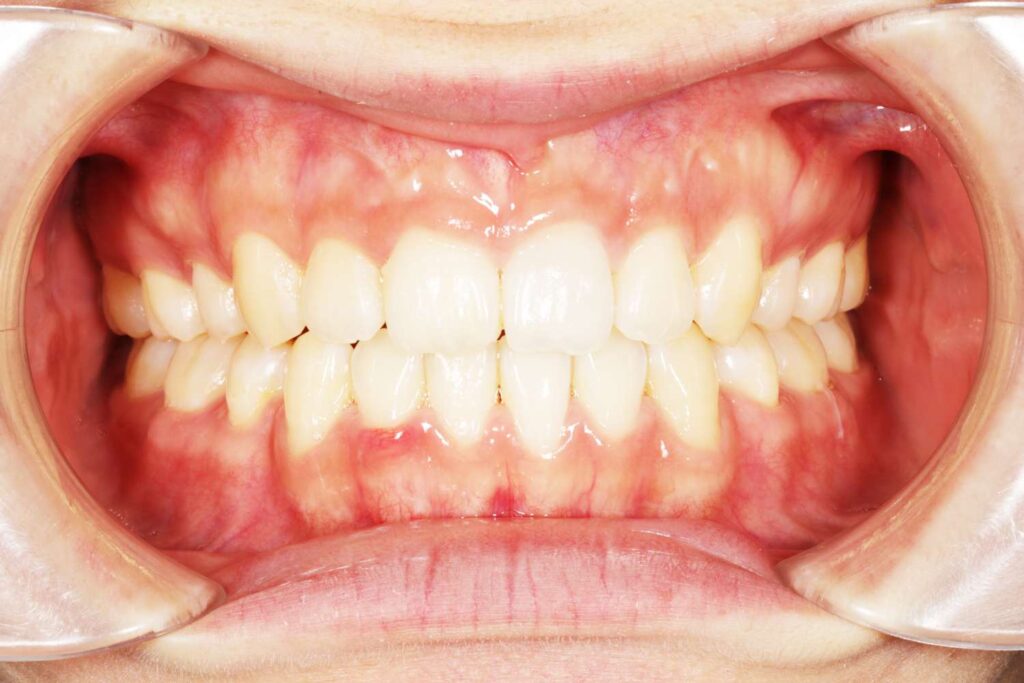

Before

After

年齢 10代

治療装置 上下とも裏側の矯正装置(フルリンガル)

治療内容 非抜歯

治療期間 2年8か月

リスク 歯の移動に伴う痛み、歯肉退縮、歯根吸収、歯肉炎、虫歯

主訴 八重歯が気になる

症状 叢生(ガタガタ)

治療回数 35回程度

総額費用 140万円程度